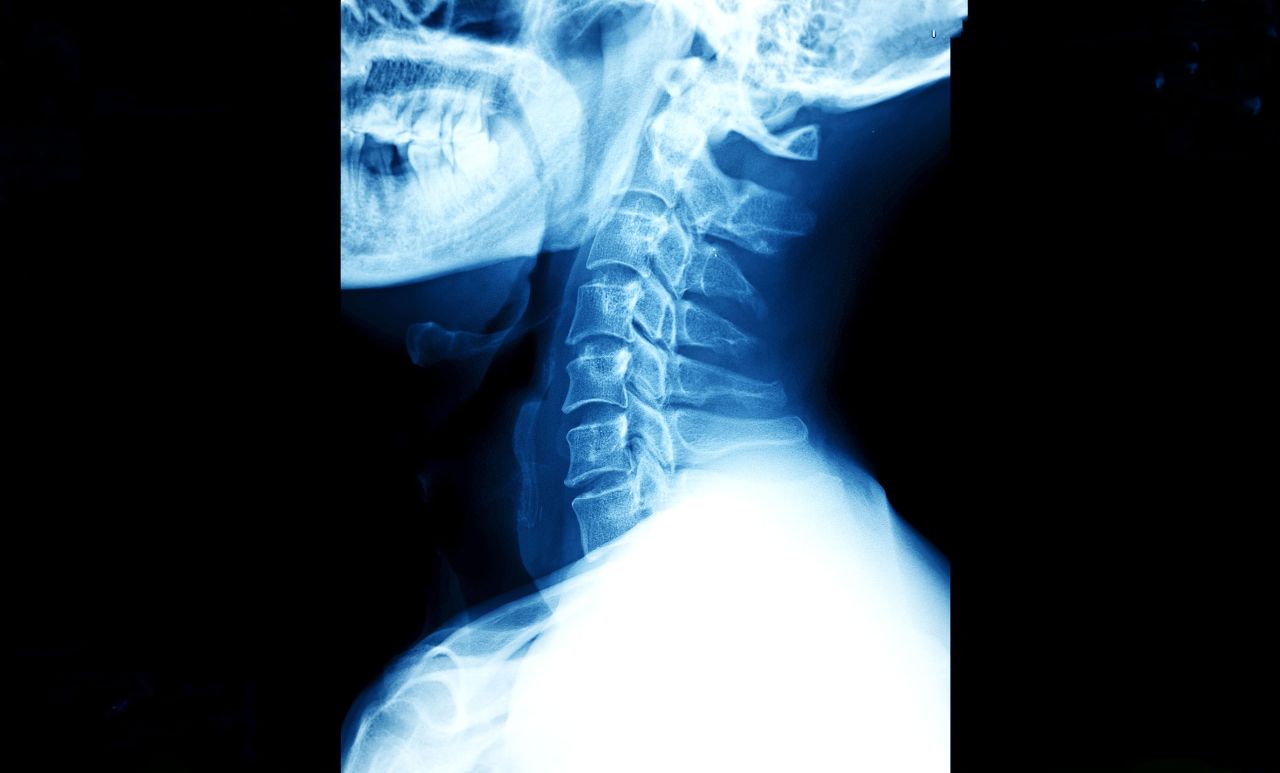

Cervical Disc Surgery: Replacement vs. Fusion for Neck Pain